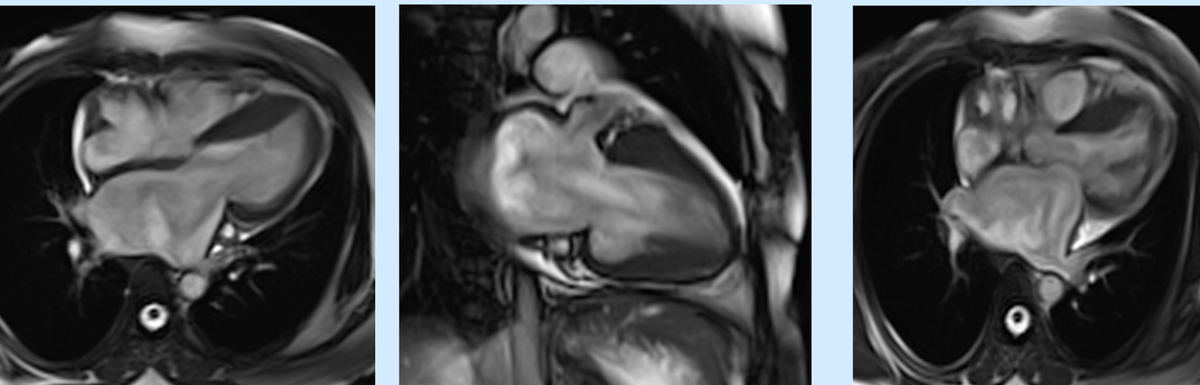

Restrictive Cardiomyopathy